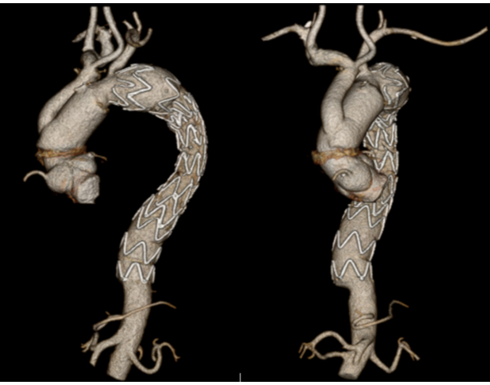

Figure 3. Postoperative CT scan demonstrating the ascending aorta and zone II aortic arch repair with debranching, and prior descending thoracic aorta stent graft. CT (computed tomographic).